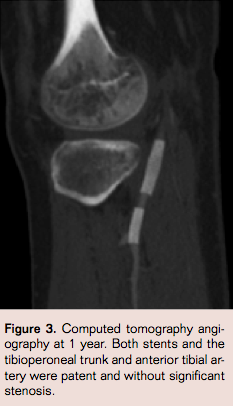

Follow-up at 18 months revealed palpable posterior tibial and dorsalis pedis pulses. Noninvasive studies showed no evidence of stenosis with triphasic waveforms and normal Ankle Brachial Index of the left leg. Computed tomographic angiography scan was obtained at 1 year, which confirmed that the reconstruction was patent (Figure 3).